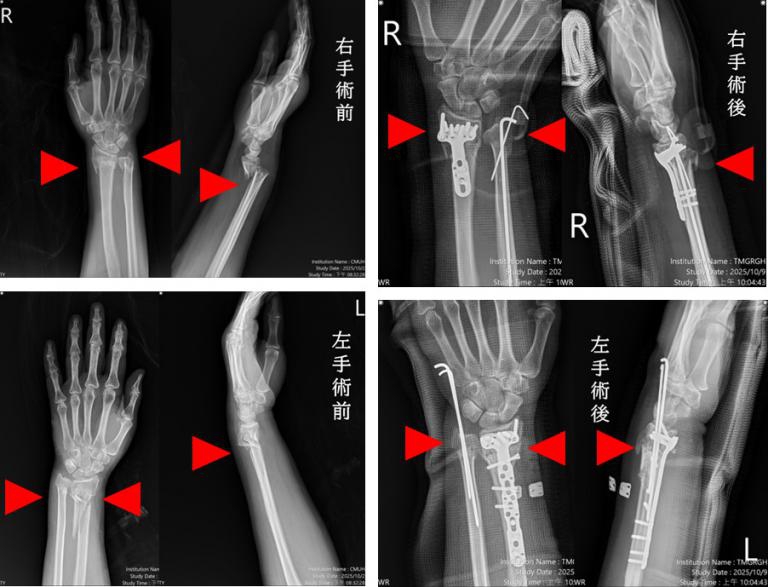

市醫機器人微創脊椎中心助理副院長暨骨科主任張建鈞表示,這名住嘉義的患者經急診救治,診斷為粉碎性複雜性骨折,由骨科部蘇伯翰、江晟弘、毛睿廷三位主治醫師同步進行左右手微創手術,僅一小時即完成四處骨折修復。

蘇伯翰醫師指出,該名傷患送至本院急診後,即時進行復位與石膏固定,並於24小時內安排開刀,採用「多主治協同手術模式」,由三位主治醫師同時操作左右手四處骨折微創手術,縮短手術時間至約一小時,協同分工可加快病患恢復速度,並提升安全性。患者傷口小、出血少,隔天即可開始復健,三天後平安出院,恢復良好。